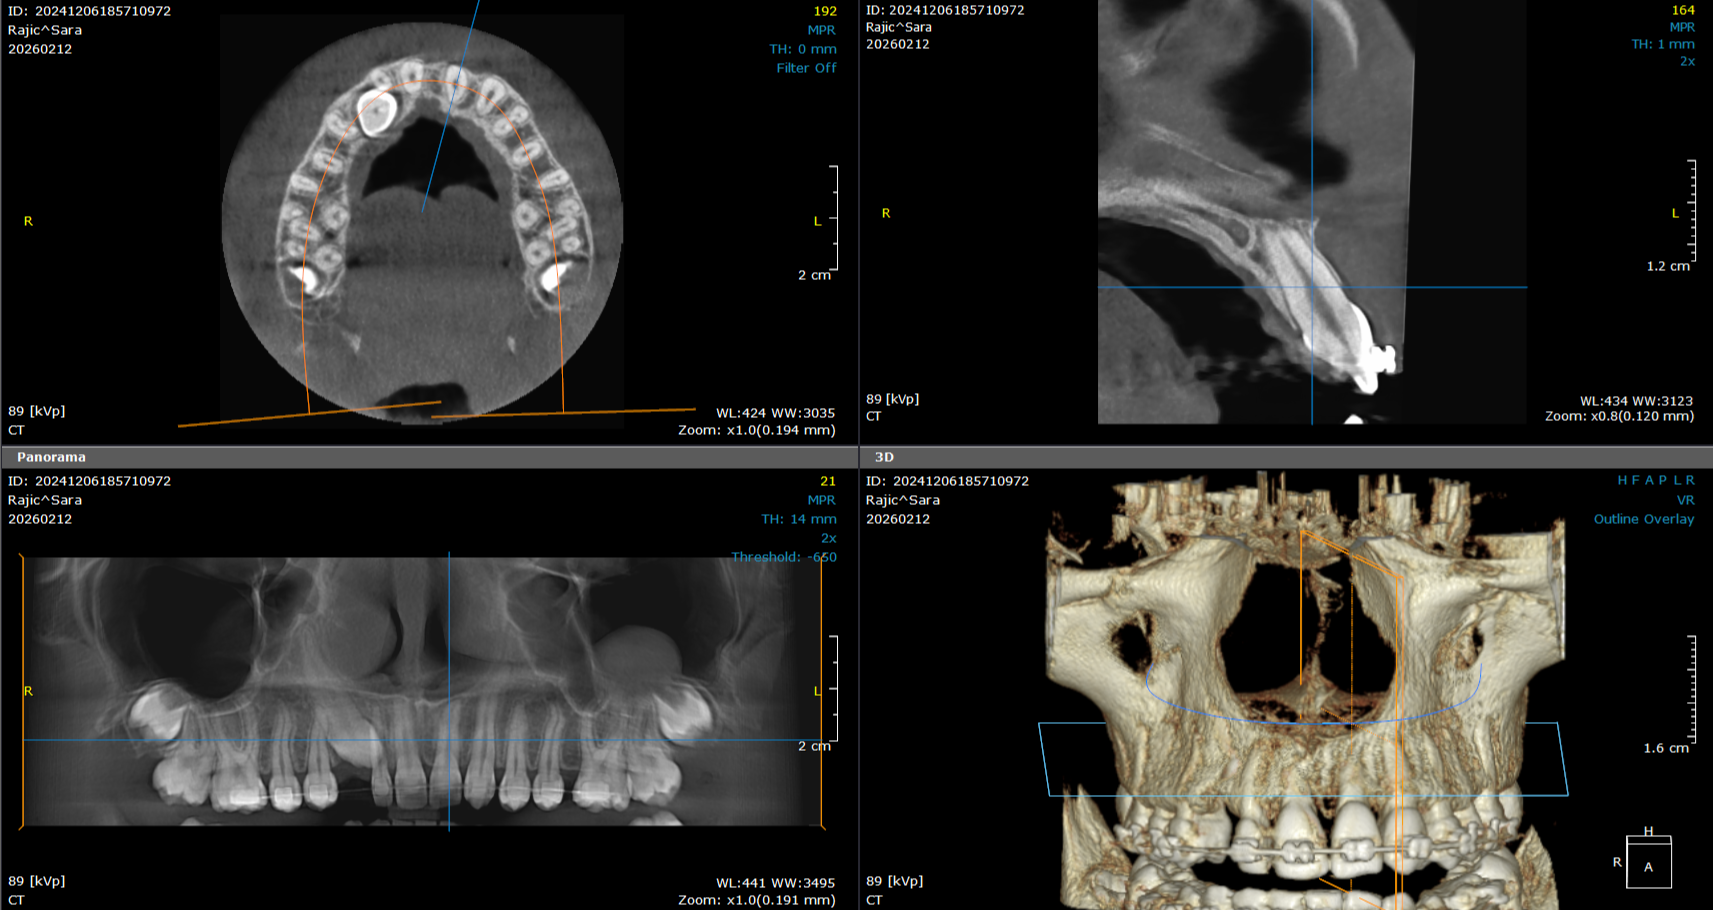

3D snimanje zuba predstavlja savremenu dijagnostičku metodu u stomatologiji koja omogućava trodimenzionalni prikaz zuba, vilice i okolnih anatomskih struktura. Ova tehnologija, poznata kao CBCT (Cone Beam Computed Tomography), pruža izuzetno precizne informacije koje stomatolozima pomažu u planiranju terapije i izvođenju složenih stomatoloških procedura.

Za razliku od klasičnih 2D snimaka, 3D snimci omogućavaju detaljan prikaz kosti, položaja zuba, nervnih kanala i sinusa, što je posebno važno kod planiranja ugradnje implantata, ortodontske terapije, endodontskog lečenja i hirurških intervencija.

Detaljan prikaz položaja zuba i vilica pomaže ortodontima u planiranju terapije i praćenju razvoja zuba.

PROCENA POLOŽAJA UMNJAKA

3D snimak omogućava precizno određivanje položaja impaktiranih umnjaka i odnosa sa nervima.